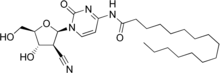

| Other names | N-[1-[(2R,3S,4S,5R)-3-Cyano-4-hydroxy-5-(hydroxymethyl)oxolan-2-yl]-2-oxopyrimidin-4-yl]hexadecanamide |

| Formula | C26H42N4O5 |

| Molar mass | 490.645 g·mol−1 |

Sapacitabine is an orally available nucleoside analog prodrug of 2′-C-cyano-2′-deoxy-1-β-D-arabino-pentofuranosyl-cytosine (CNDAC) that acts through a dual mechanism. CNDAC lasts longer in the bloodstream by being metabolized from sapacitibine than it would do so by being directly administered.[3]

The compound interferes with DNA synthesis by causing single-strand DNA breaks due to CNDAC being incorporated into DNA during replication or repair,[3] then inducing arrest of the cell division cycle at G2 phase.